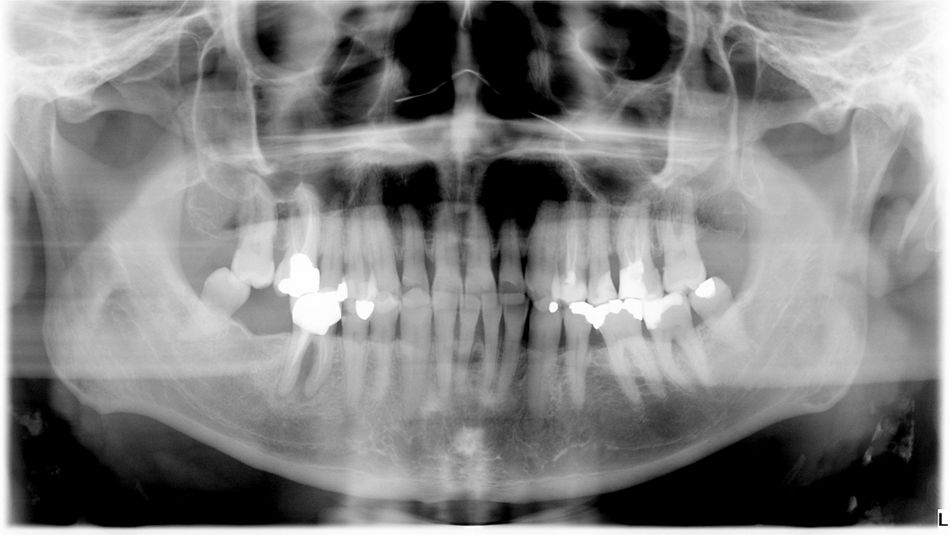

The patient was diagnosed by 3D CT scan and radiograph during a routine control of a classic first molar.  The clinical signs necessitated tooth extraction followed by immediate implantation, socket gap filling and placement of a sealing socket abutment to support anatomical structures.

1. Radiograph of initial situation.

1